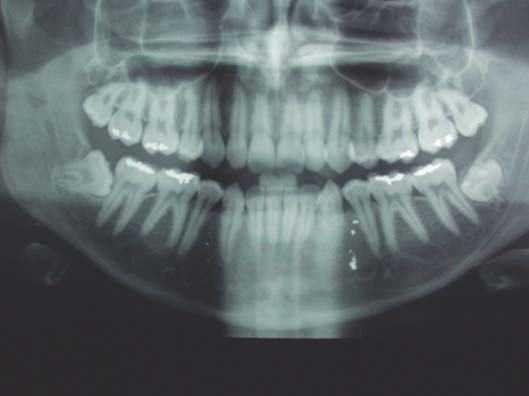

En el estudio radiológico (ortopantomografía) se observa el depósito de material metálico en dicha localización y en regiones de molares posteriores (fig. 3). No se realizó estudio histológico.

Figura 3.